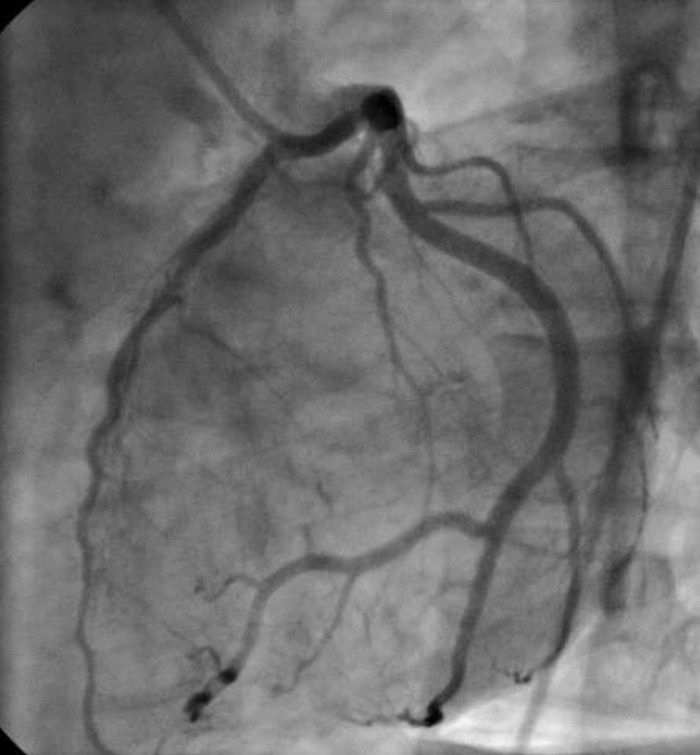

11 / 15Choroby serca - koronarografia

Obraz

© cath lab, lic. CC BY 3.0

Koronarografia

Koronarografia jest to badanie naczyń wieńcowych cewnikiem wprowadzonym przez tętnicę udową. Następnie dodawany jest kontrast umożliwiający uwidocznienie tętnic za pomocą promieniowania rentgenowskiego. Obrazy z angiografii dokładnie wskazują zakres i ciężkość wszelkich zatorów tętnic wieńcowych.